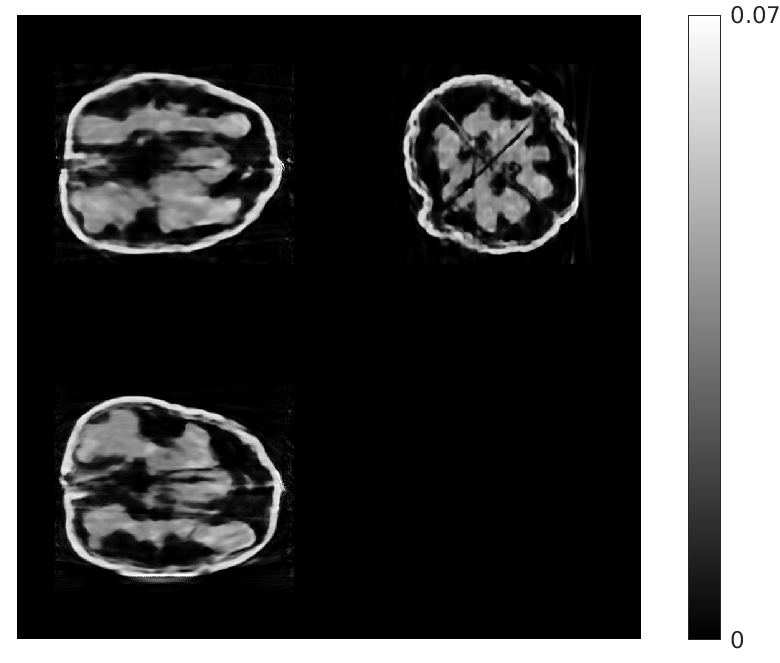

Fig. 2 gives an example reconstruction for 8 views (walnut 1 in Table I), showing central slices through the walnut in all three orientations (sagittal, coronal and transverse). The proposed algorithm provides significantly higher quality reconstructions than the other methods. This is particularly evident in the extent to which our algorithm is able to restore the finer features of the walnuts, and has fewer artifacts.

| Ground Truth Test Volume | Ground Truth Training Volume |

| (a) (NMAE) | (b) (n/a) |

| FDK | EP Regularized Recon. |

| (c) (0.77) | (d) (0.45) |

| Destreaking CNN | Proposed |

| (e) (0.40) | (f) (0.26) |